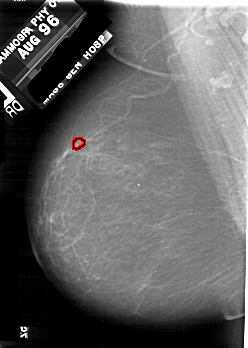

FILE: A_1731_1.LEFT_CC.OVERLAY

TOTAL_ABNORMALITIES 1

ABNORMALITY 1

LESION_TYPE CALCIFICATION TYPE PLEOMORPHIC DISTRIBUTION CLUSTERED

ASSESSMENT 4

SUBTLETY 2

PATHOLOGY MALIGNANT

TOTAL_OUTLINES 1

BOUNDARY